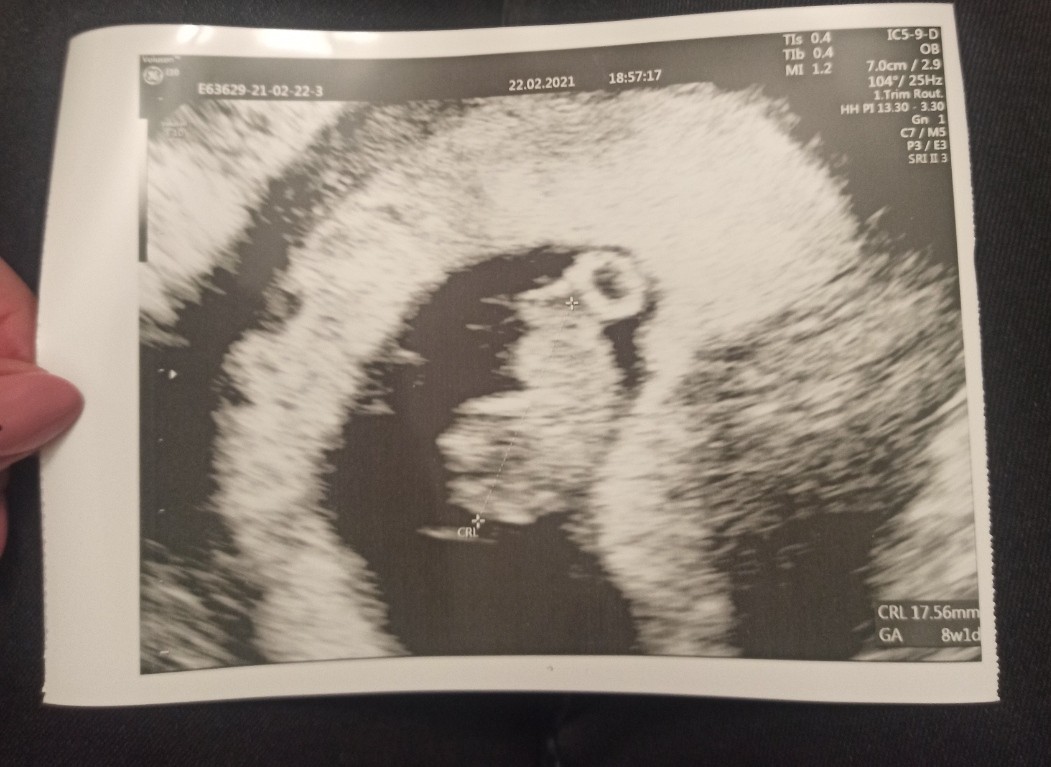

Moja Fasolka nadal rośnie i jest wszystko super ❤️ ma 2 cm, serduszko bije, ma rączki i nóżki i to wszystko jest takie genialne! 🥰

W poniedziałek byłam też u docelowego lekarza, pokażę to zdjęcie to lepiej widać, niż na tym dzisiejszym.